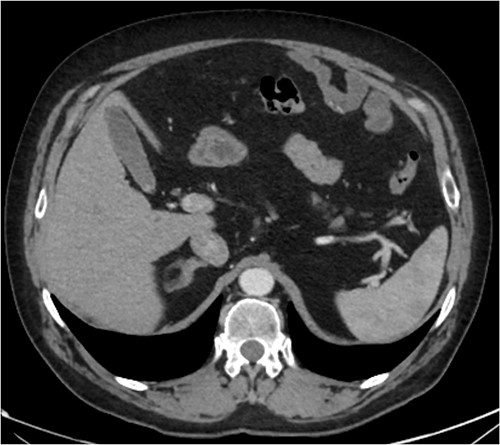

A CT abdomen-pelvis (CT-AP) revealed an acute haematoma inferolateral to the third part of the duodenum and another at the root of the mesentery. High density fluid related to the mesenteric bleed was also seen extending from the right para-colic gutter into the pelvis and in the peri-hepatic region. The patient was admitted under general surgery, stabilized with intra-venous fluid resuscitation, co-amoxiclav and metronidazole and cross matched for four units of blood. A CT-angiogram demonstrated acute haemorrhage throughout the abdomen with a 104 x 62 mm haematoma arising centrally at the level of L2 within the mesenteric fat (Fig. 1). The haematoma did not appear to originate from any specific mesenteric vessels but was related to some mid and distal jejunal loops. The angiogram also showed discontinuity when tracing the proximal and mid jejunal loops inferiorly, extensive haemorrhagic peritoneal fluid around the liver extending inferiorly (Fig. 2) and a small amount of peri-splenic haemorrhagic fluid. Curved reformatting of the angiogram revealed no abnormalities within the superior mesenteric artery (Fig. 3).

CT angiogram showing a peri-hepatic haematoma. Figure 2 is an axial section taken from the patient’s initial CT angiogram of the abdomen and pelvis. A large crescent shaped peri-hepatic haematoma is highlighted by the arrow displayed.